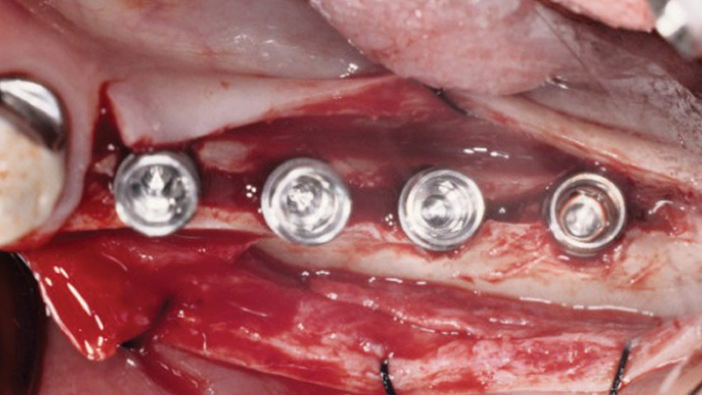

Clinical case: Installation of dental implants in complicated anatomic conditions using crest lifting methods

- Courtesy of Dr.Alexander Lysov, Russia -

Keywords

AnyRidge, complicated anatomic conditions, crest lift, MICA Kit, Dr. Alexander Lysov, bone regeneration, GBR, #26, maxillary posterior

Products:

AnyRidge implant system, MICA Kit

“Thin ridge expansion with minimally invasive surgery!

Use SmarThor & AnyRidge to place a wider diameter implant with minimal drilling after ridge splitting, even in thin ridge under 2mm! “